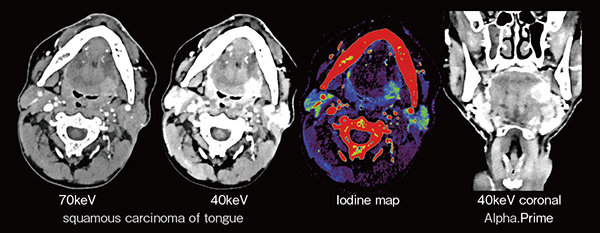

頭頸部画像診断では咽頭や口腔の軟部組織の描出が重要であり,Spectral解析による高コントラスト画像によって病変検出能が向上する。

舌基部に腫瘍が浸潤した症例(図3)では,40keV画像によって造影剤と周囲組織のコントラストが向上し,腫瘍の境界が明瞭である。ヨードマップでも腫瘍の境界が明瞭であり,高解像度画像によって舌内部の筋束や腫瘍の深部浸潤も評価できる。

図3 Spectral解析による舌基部の腫瘍浸潤の評価